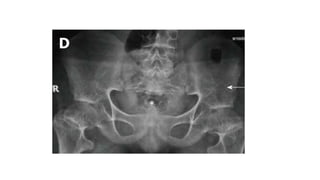

PELVIS

• Short and broad pelvic cavity- Champagne glass pelvis

• Squaring of iliac wings with rounded corners- Elephant ear shaped

iliac wings

• Horizontal and flat acetabuli

• Small sacrosciatic notch; large, anteriorly protruding sacral

promontory

PELVIS • Short andbroad pelvic cavity- Champagne glass pelvis • Squaring of iliac wings with rounded corners- Elephant ear shaped iliac wings • Horizontal and flat acetabuli • Small sacrosciatic notch; large, anteriorly protruding sacral promontory